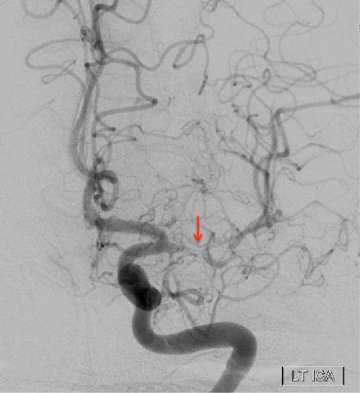

Moyamoya Figure 1

The figure shows the angiogram of a patient with intracranial arterial stenosis. The arrow indicates the narrow segment of the middle cerebral artery.